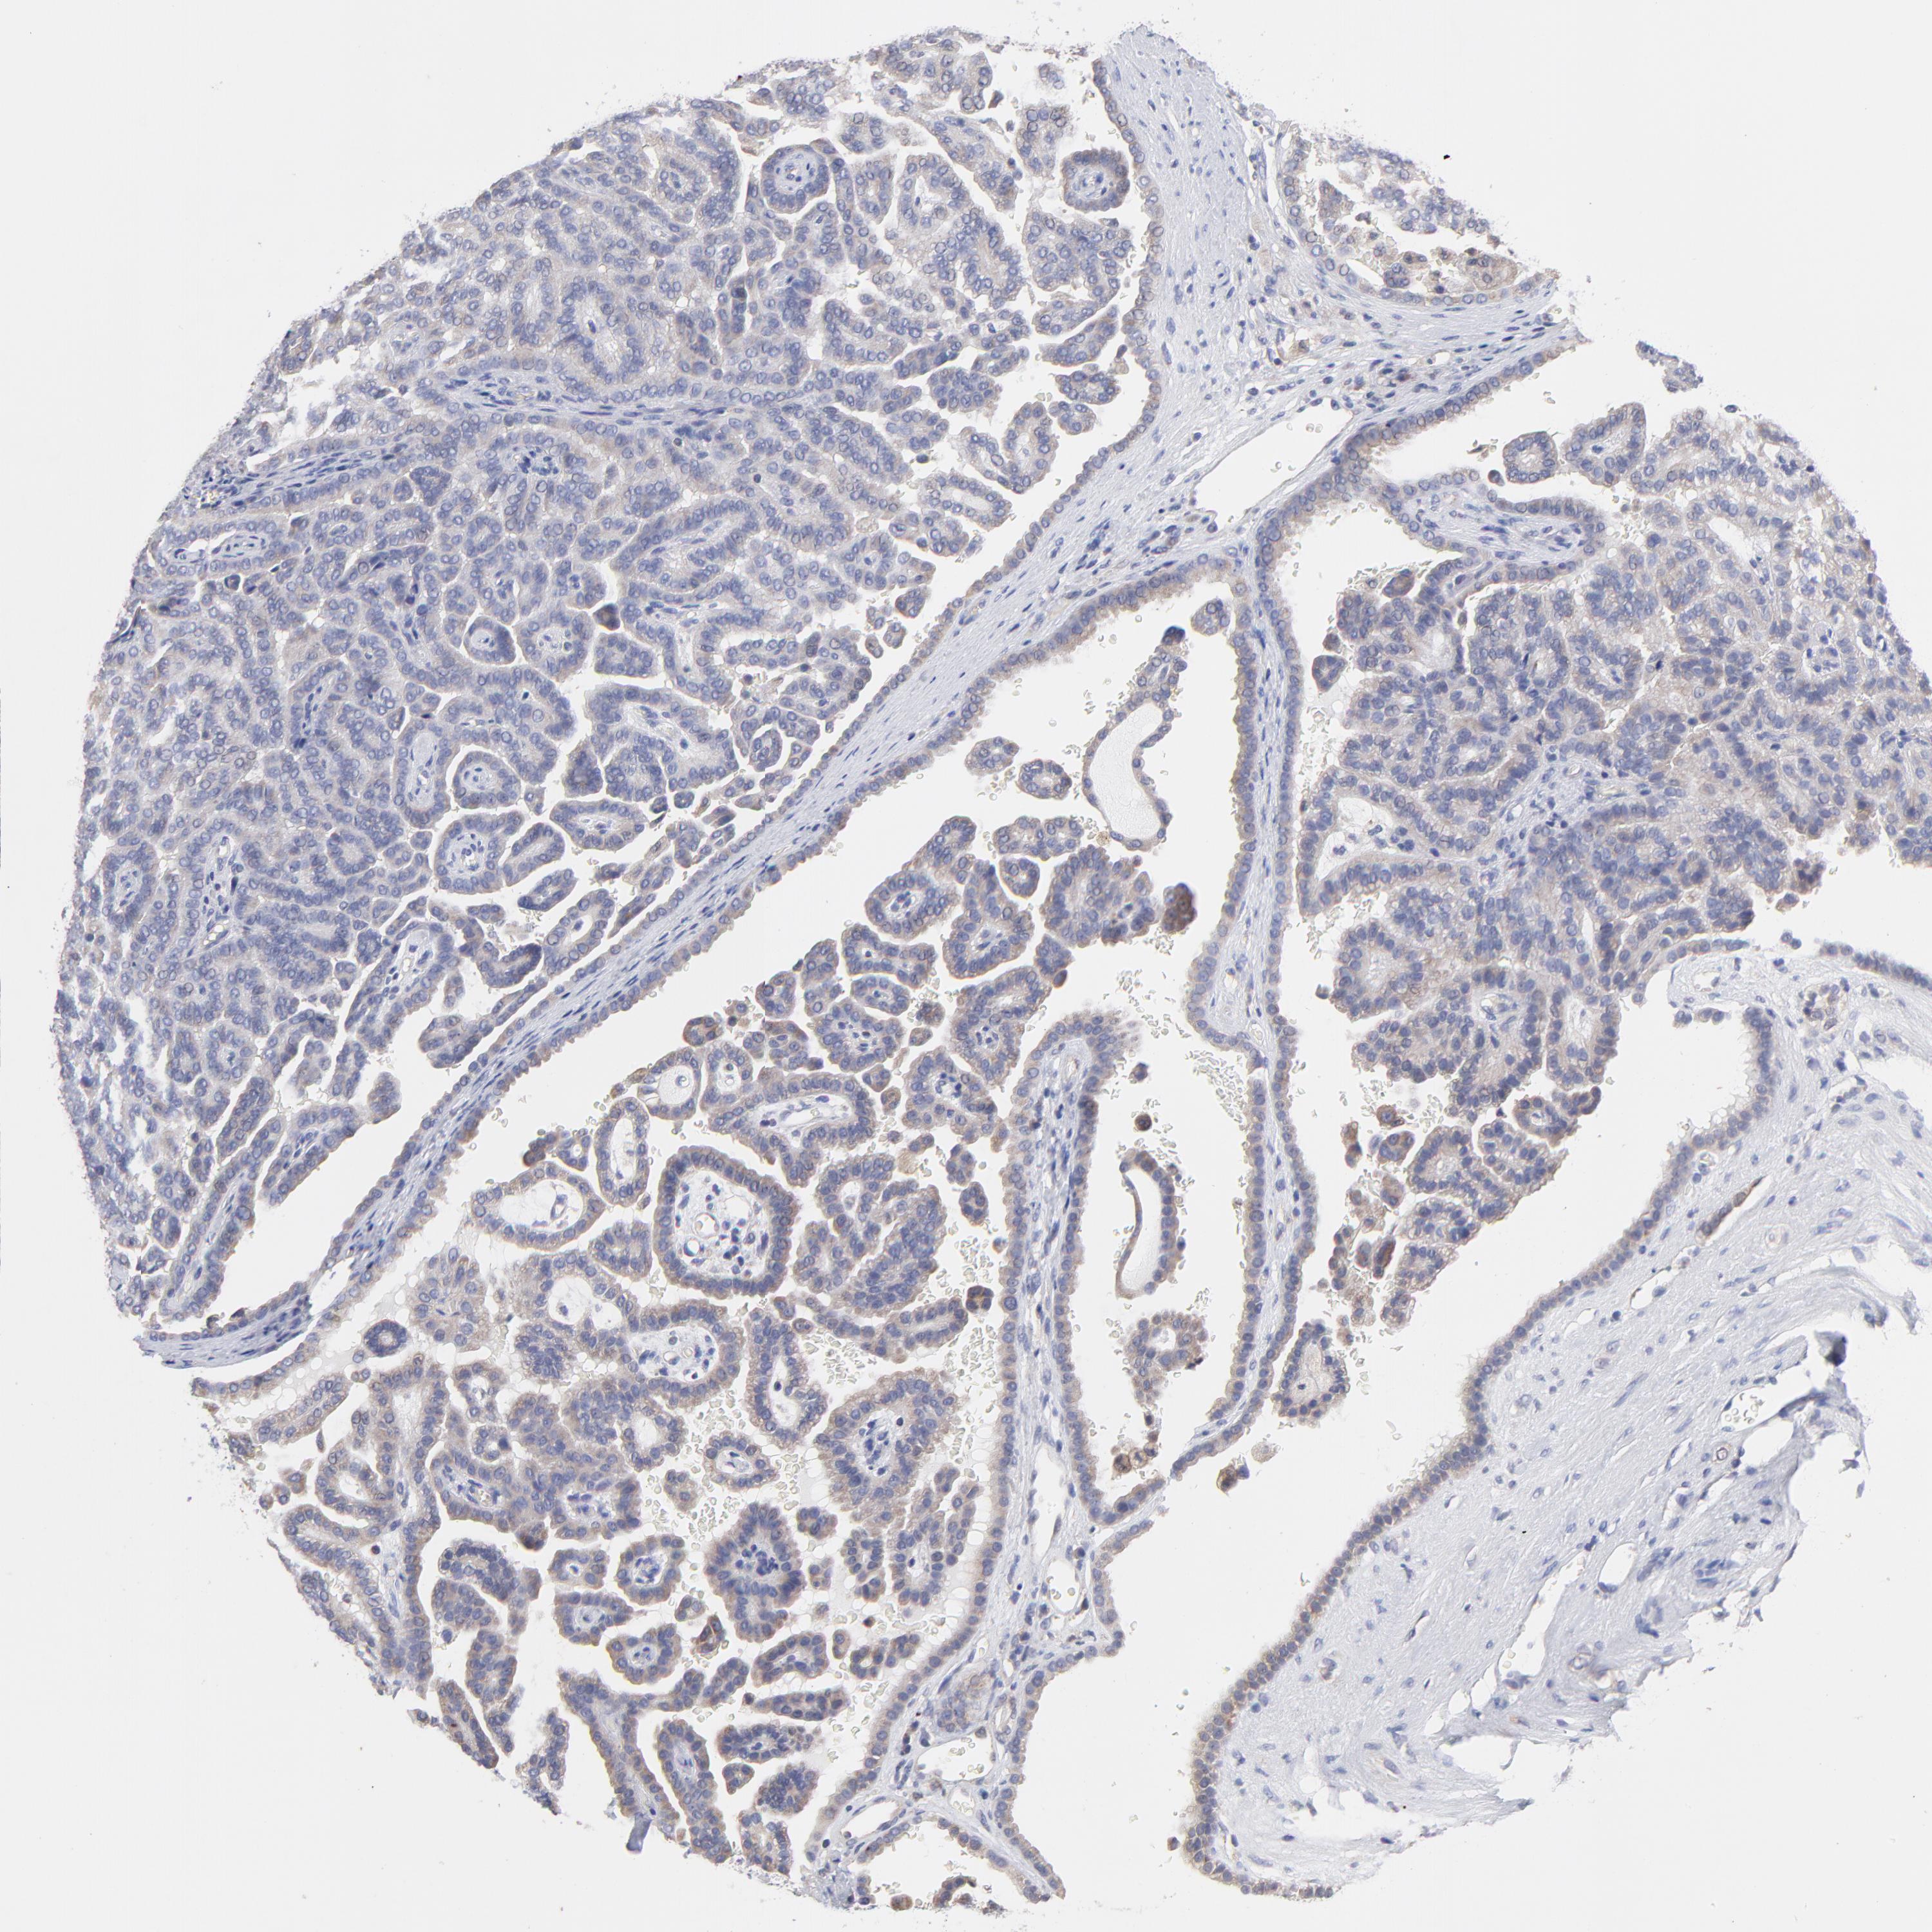

KIDNEY RENAL CLEAR CELL CARCINOMA (VALIDATION) - Interactive survival scatter ploti

The Survival Scatter plot shows the clinical status (i.e. dead or alive) for all individuals in the patient cohort, based on the same data that underlies the corresponding Kaplan-Meier plots. Patients that are alive at last time for follow-up are shown in blue and patients who have died during the study are shown in red.

The x-axis shows the expression levels (FPKM) of the investigated gene in the tumor tissue at the time of diagnosis. The y-axis shows the follow-up time after diagnosis (years). Both axes are complimented with kernel density curves demonstrating the data density over the axes. The top density plot shows the expression levels (FPKM) distribution among dead (red) and alive patients (blue). The right density plot shows the data density of the survived years of dead patients with high and low expression levels respectively, stratified using the cutoff indicated by the vertical dashed line through the Survival Scatter plot. This cutoff is automatically defined based on the FPKM cutoff that minimizes the p-score. The cutoff can be changed by dragging the vertical line or by entering a cutoff value in the square labeled "Current cut-off".

Under the Survival Scatter plot the p-score landscape (black curve; left axis) is shown together with dead median separation (red curve; right axis). Dead median separation is the difference in median mRNA expression between patients who have died with high and low expression, respectively. It is calculated as follows: median FPKM expression of dead patients with high expression - median FPKM expression of dead patients with low expression. This is intended to aid the user in visually exploring custom cutoffs and the associated p-scores and dead median separation.

Individual patient data is displayed and can be filtered by clicking on one or more of the category buttons on the top of the page. Categories describing expression level and patient information include: high, low, alive, dead, female, male and tumor stages. The scale of the x-axis can be toggled between linear and log-scale by clicking on the "x log" button. Mouse-over function shows TCGA ID, patient information and mRNA expression (FPKM) for each patient.

& Survival analysisi

Kaplan-Meier plots summarize results from analysis of correlation between mRNA expression level and patient survival. Patients were divided based on level of expression into one of the two groups "low" (under cut off) or "high" (over cut off). X-axis shows time for survival (years) and y-axis shows the probability of survival, where 1.0 corresponds to 100 percent.

PCMT1 is not prognostic in Kidney Renal Clear Cell Carcinoma (validation)

Best expression cut offi

Based on the FPKM value of each gene, patients were classified into two groups and association between prognosis (survival) and gene expression (FPKM) was examined. The best expression cut-off refers the FPKM value that yields maximal difference with regard to survival between the two groups at the lowest log-rank P-value. Best expression cut-off was selected based on survival analysis .

When clicking on this number, the vertical dashed line indicating cut-off, the interactive survival plot, and the Kaplan-Meier curve will be adjusted to show results based on the best expression cut-off.

: 46.36

P scorei

Log-rank P value for Kaplan-Meier plot showing results from analysis of correlation between mRNA expression level and patient survival.

N/A

TCGA RNA samplesi

RNA-seq data is reported as average FPKM (number Fragments Per Kilobase of exon per Million reads), generated by the The Cancer Genome Atlas (TCGA) .

Normal distribution across the dataset is visualized with box plots, shown as median and 25th and 75th percentiles. Points are displayed as outliers if they are above or below 1.5 times the interquartile range. FPKM values of the individual samples are presented next to the box plot.

Average pTPM 49.3

Number of samples 100